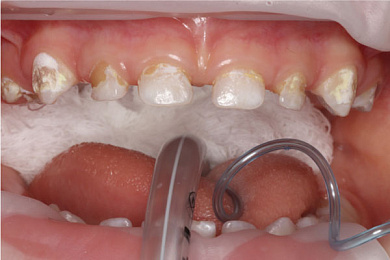

Молочные зубы чувствительны к возникновению кариеса. По этой причине гигиена полости рта у малышей играет важную роль для предотвращения его появления. Даже самая качественная зубная паста не сможет гарантировать защиту от разрушения зубов. Кариес, оставленный без лечения в надежде на скорую смену молочных коренными, способен уничтожить зубы ребенка всего за несколько лет, а кроме этого вызывает осложнения, которые влияют на формирование постоянных зубов.

Традиционное лечение кариеса подразумевает использование бормашинки. Это не самая приятная процедура, вызывающая болезненные ощущения и дискомфорт, особенно когда речь идет о детях. К сожалению, в запущенном состоянии без неё кариес не победить.

Если же обратиться с ребенком к стоматологу на ранней стадии развития, то возможно лечение с применением технологии ICON, которая состоит в нанесении на поврежденный участок специального композитного материала без предварительного бурения.